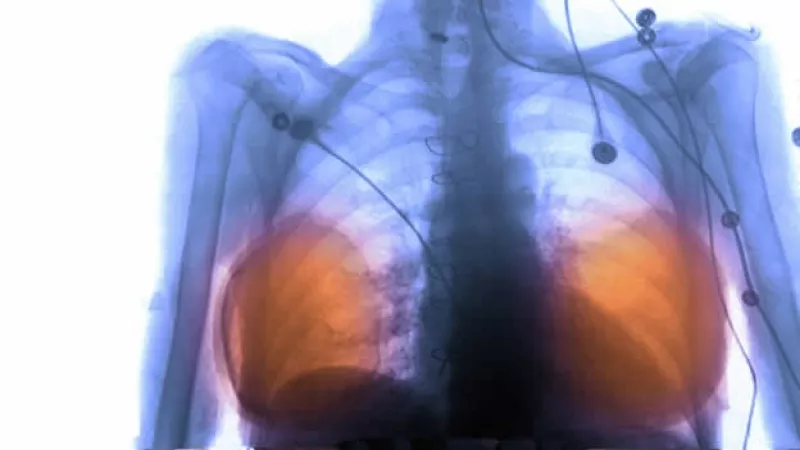

silicon implant breasts seno pecho xray